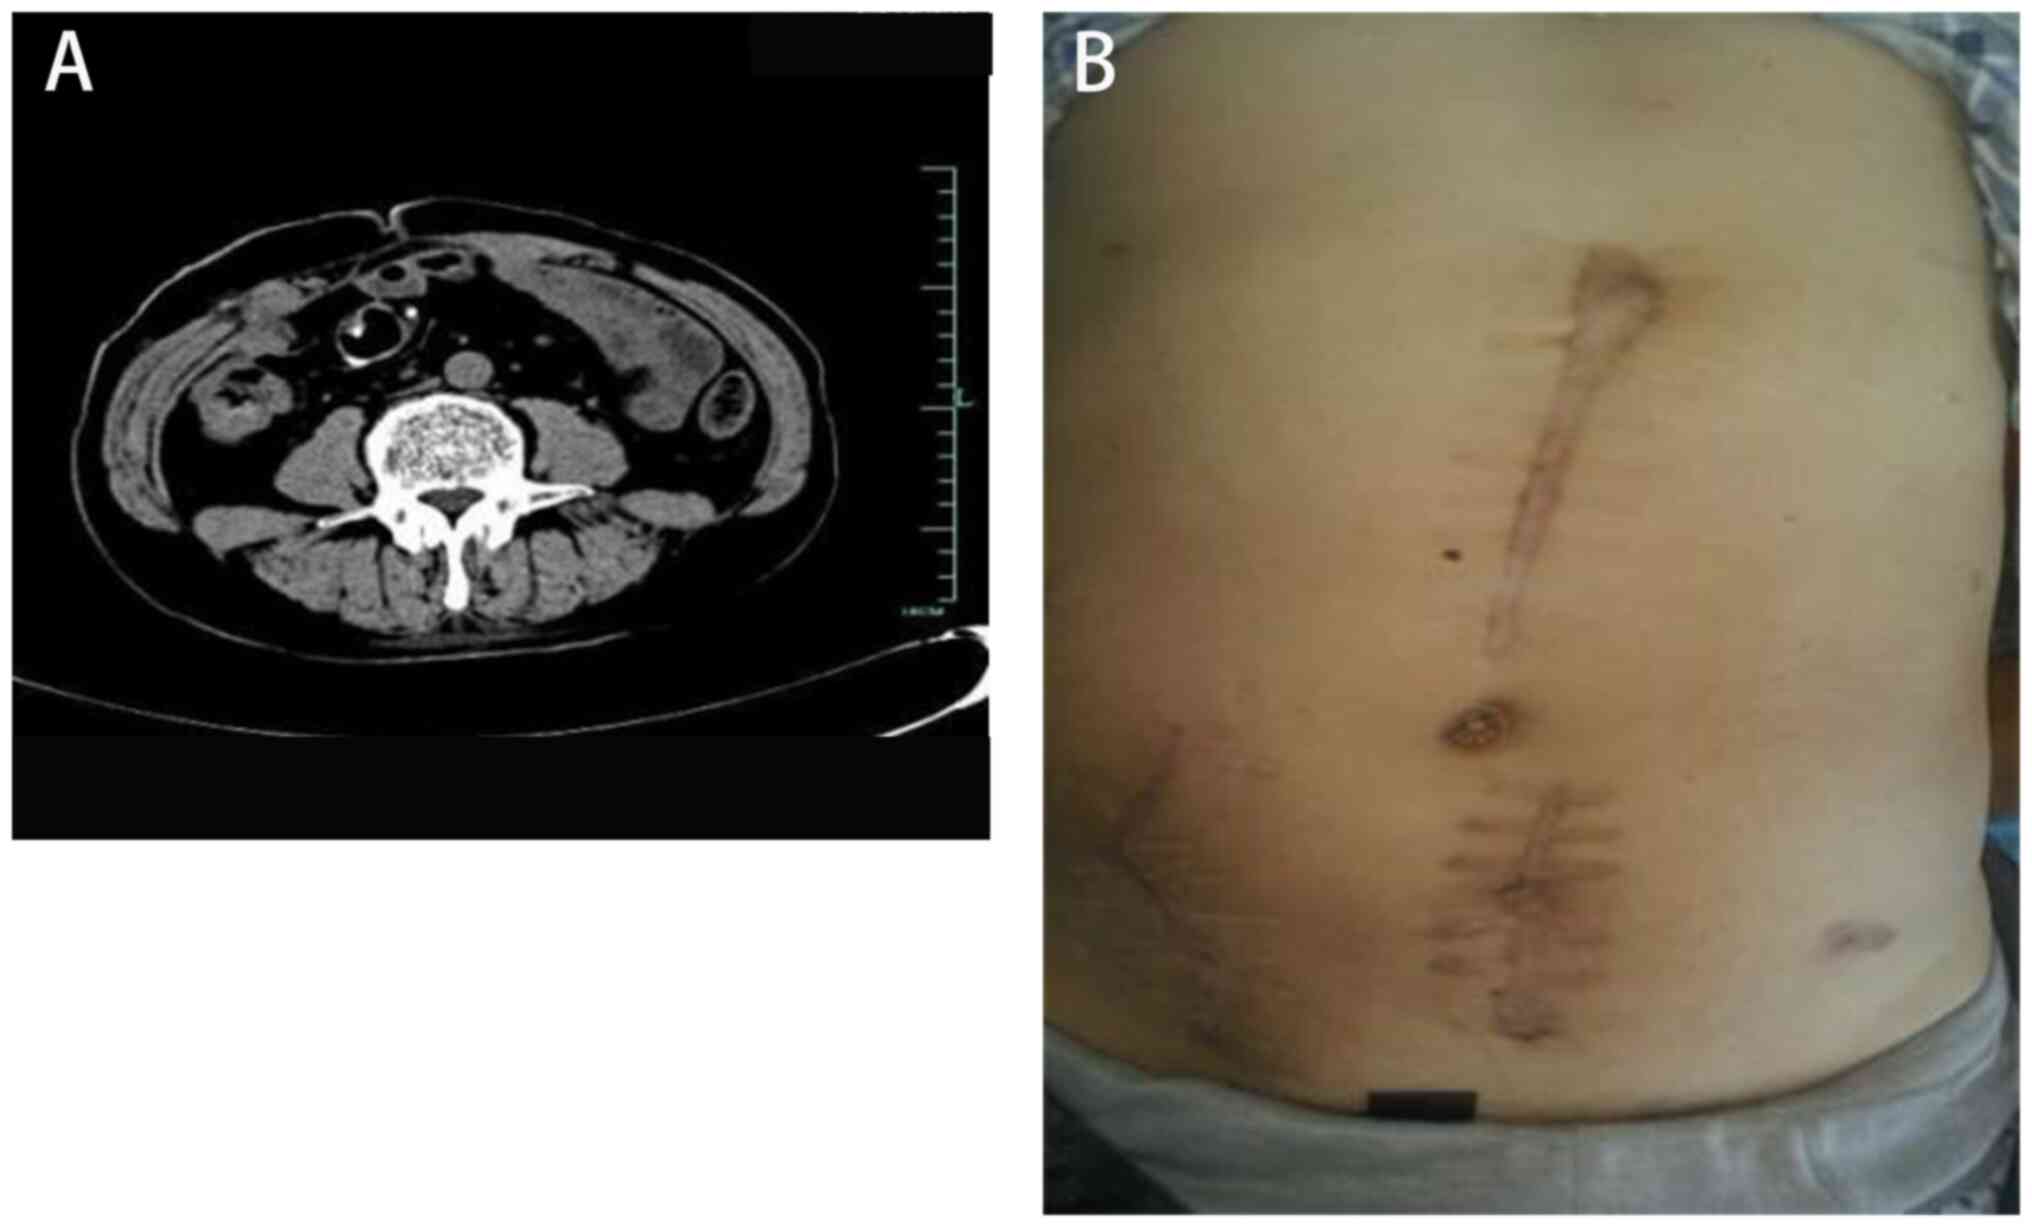

The third stage of treatment involved the insertion of drainage stents into the colon (6-10 weeks after admission). Two colon drainage tubes, each measuring 12 cm in length, were utilized. Multiple side holes were cut along the tubes, which were then bound together and fully inserted into the colonic cavity. To prevent stent displacement due to intestinal peristalsis, they were suspended and secured in place using 10# silk thread at the midpoint. A total of 8 weeks after admission, a small amount of leakage was observed at the incision site on the upper abdomen, and the fixed thread was removed. A total of 10 weeks after admission, skin leakage in the upper abdominal colon completely healed (Fig. 3).

Figure 3

Insertion of drainage stents into the colon. (A) Illustrative image. (B) Radiographic examination. (C) Computed tomography examination. (D) Skin fistula healing.

Finally, the fifth stage of treatment involved small intestinal fistula recovery. A total of 1 month after the removal of the colon drainage stent, a small intestinal fistula reversion operation was performed. Following the procedure, the patient experienced a successful recovery. Physical examination and abdominal computed tomography revealed favorable progress, and the patient was discharged (Fig. 5). The patient received satisfactory treatment outcomes through diligent care provided by the medical team and nursing staff, effectively averting further complications, such as fistula formation and larger trauma (Fig. 6). The latest follow-up of the patient was in June 2023, and the patient is currently undergoing an annual follow-up. The follow-up entails blood tests to assess routine blood work, liver function, kidney function and electrolyte levels, as well as a full abdominal computed tomography or magnetic resonance imaging scan and physical examination. The patient is currently in good condition and is satisfied with the recovery.

Figure 5

Images taken after the small intestinal stomal return into the abdominal cavity. (A) Computed tomography examination. (B) Skin healing.